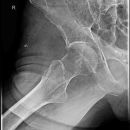

Hüfte nach Lauenstein I (45°)

KONTRAINDIKATION: frische Fraktur und Luxation

Gute Beurteilung des Hüftkopfes, der Pfanne und des Schenkelhalses. Der Trochanter major überdeckt weitgehend den Schenkelhals.